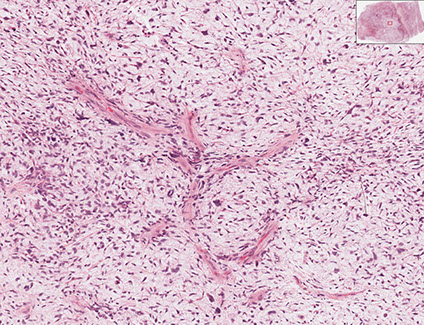

Deep Fibromatosis (Desmoid tumors)

Infiltrative, sometimes painful lesion of clonal fibroblasts in deep ST/muscle c irregular borders that frequently recur but don't met

- 2nd to 5th decades (esp head and neck if in kids) MC in shoulder (1/4), chest wall, thigh if outside abdomen

- 3 F > 1 M; usually as an abdominal wall mass

- not as common as superficial fibromatosis

- can be lethal 2/2 mass effects when in head and neck of kids

- may be familial and assoc c Gardner's syndrome

Micro: Bland long sweeping fascicles (usually that go all the way across the microscope field) c bipolar fibroblasts / myofibroblasts  c amphophilic cytoplasm that blends into surrounding collagen and have very open chromatin and large single prominent nucleolus

- has thick-walled, intermediate-sized BVs between fascicles, sometimes with perivascular edema

- cancer cells are bwt super thick fibrous bands (is more collagenous and less cellular than nodular fasciitis)

- regenerating muscle can form MNGC-oid cells

- few mits, no atypia

Cyto: bland individual/single spindle cells c long fusiform nuclei and metachromatic matrix material possibly in a fascicular pattern

IHC: (+) vimentin, SMA and CD117 (variable, can be a pitfall for GISTs!!!), nuclear B-catenin (sensitive but not specific; see genes below), ER-beta

- negative: keratin, S100, CD34, ALK, desmin, ER-alpha, PR, MUC4

Genes: Clonal, assoc c Wnt/B-catenin (APC-B catenin - Tcf) pathway, trisomies 8 and/or 20, APC inactivation

- APC binds B-catenin, in Wnt pathway, so inactivation of APC causes build-up of nuclear B-catenin (which causes a positive nuclear B-catenin stain; thus reactive scars and nod fasc has positive cytoplasmic B-catenin, not nuclear B-catenin like those seen in clonal fibromatosis)

- pts c FAP / Gardner syndrome c germline APC mutations on cr 5q are predisposed, and are intra-abdominal

- sporadic tumors are extra-abdominal and assoc c CTNNB1 mutation

Tx: Wide-margin excision (tends to recur)

- chemo/rads can be helpful

DDx: GISTs are more cellular, are located within the muscle layer, and have larger endothelial cells; Leiomyosarcoma have nuclear pleomorphism, more eosinophilic cytoplasm, and perpendicular fascicles

Desmoid fibromatosis with long sweeping fascicles

Desmoid fibromatosis with medium-sized BV